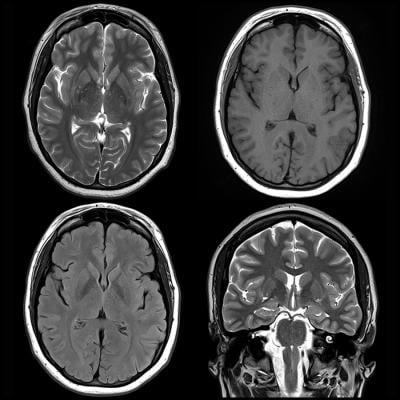

With the help of his West China Hospital colleagues Huaiqiang Sun, Ph.D., and Ying Chen, M.D., Ph.D., Gong studied 83 children, ranging in age from of 7 to 14, with newly diagnosed and never-treated ADHD. The group included children with the inattentive ADHD subtype and the combined subtype. Researchers compared brain MRI results with those of a control group of 87 healthy, similarly aged children. The researchers used a relatively new feature that allowed them to screen relevant radiomics signatures from more than 3,100 quantitative features extracted from the gray and white matter.

No overall difference was found between ADHD and controls in total brain volume or total gray and white matter volumes. However, differences emerged when the researchers looked at specific regions within the brain. Alterations in the shape of three brain regions (left temporal lobe, bilateral cuneus and areas around left central sulcus) contributed significantly to distinguishing ADHD from typically developing controls.

Within the ADHD population, features involved in the default mode network — a network of brain regions active when an individual is not engaged in a specific task — and the insular cortex — an area with diverse functions related to emotion — significantly contributed to discriminating the ADHD inattentive subtype from the combined subtype.

Overall, the radiomics signatures allowed discrimination of ADHD patients and healthy control children with 74 percent accuracy and discrimination of ADHD inattentive and ADHD combined subtypes with 80 percent accuracy.